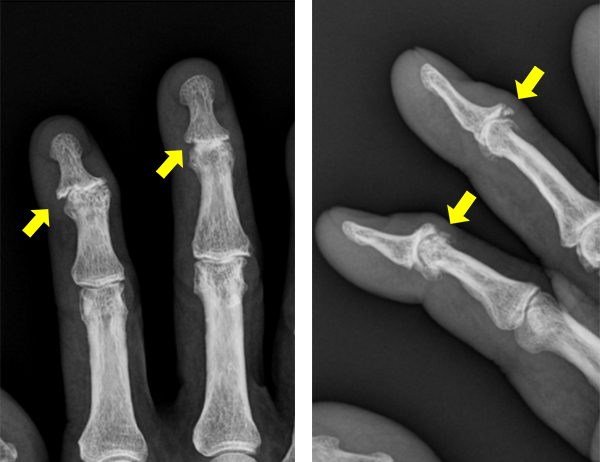

ブシャール結節

ブシャール結節では手指のPIP関節(第2関節)が腫れて痛みを感じるようになります。進行してくるとPIP関節が変形し、変形が強くなると関節の動きが悪くなってきます。

PIP関節の動きが悪くなると指が握り込めなくなるため、握力が低下します。

へバーデン結節、ブシャール結節の診断は問診や身体所見がとても大切です。当院では、問診や身体所見に加えてまず手指X線撮影を行い関節変形の評価を行います。典型例では関節の隙間が狭くなり、骨棘(こつきょく)の形成や偏位(横方向へのずれ)を認めます。なお、両手で複数のPIP関節が腫れて痛みがある場合には、関節リウマチなど膠原病の疑いがあるため、血液検査を実施します。